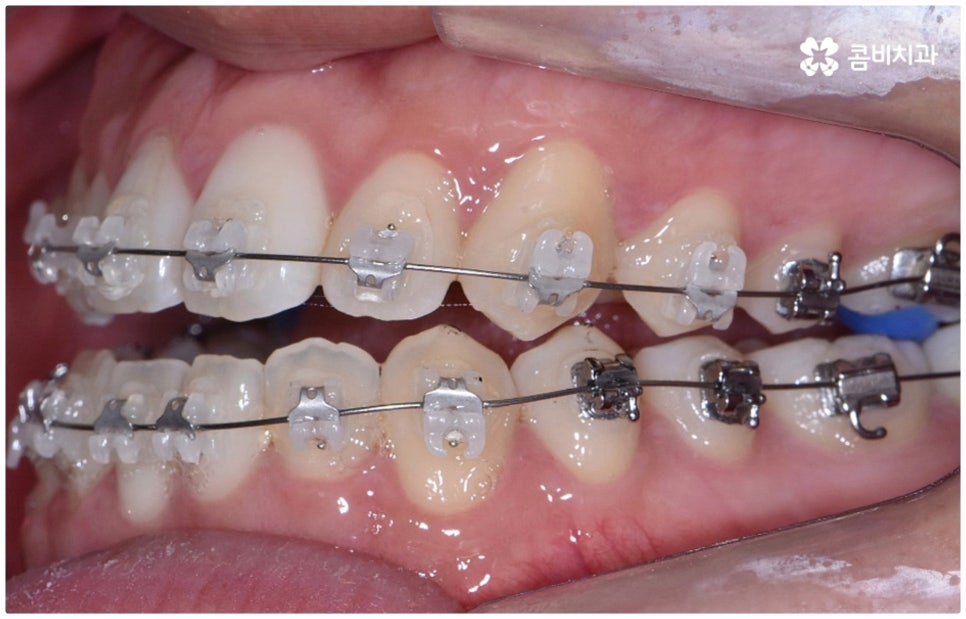

물론 교정 치료에 적기가 정해져 있는 것은 아니기 때문에 성인 이후 중장년 환자분들이라도 교정 치료가 불가능하지는 않으며 상황에 따라 비수술적인 방법으로도 얼마든지 불편함을 줄일 수 있는 경우가 있으니 정확하게 진단한 후 각자에게 맞는 교정 계획을 세워 무리하지 않게 치료를 진행하시길 바라고 있어요. 특히 턱관절과 관련된 부분을 개선하기 위해서는 양악 수술 밖에 방법이 없는 것이 아닌가 생각하셨던 분들이라면 먼저 치과에 내원하셔서 검진과 상담부터 진행해 보시면 마음의 부담을 덜 수 있어 좋을 거예요. 부정교합 3급 치열 (절단교합과 일부 반대교합이 병행되어 있음) 을 가지고 있는 성인분도 교정 치료를 통해 훨씬 자연스럽게 개선이 가능할 수 있으며, 관련 기술 개발 및 미니스크류 등 여러 장치의 발전을 통해 예전에는 적용이 어려웠던 케이스들도 이제는 교정 치료의 도움을 받을 수 있습니다.

위 사진은 이해를 돕기 위한 이미지이며, 환자의 동의하에 진행되었습니다.

전체 치료 기간은 약 18개월이 소요되었으며,

개인에 따라 출혈 및 부작용이 발생할 수 있고,

환자마다 치료 결과 및 기간이 상이할 수 있으므로,

정확한 치료 기간 및 치료 계획은

치과에서 상담을 받아보시길 권장 드립니다.